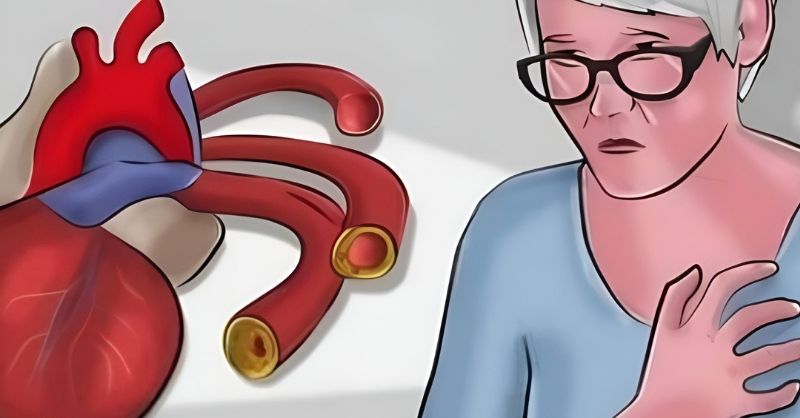

6 Vitamins to Unclog Your Arteries

Atherosclerosis is a condition where the inner walls of your arteries become damaged and clogged with a hardened substance known as plaque. This buildup narrows the arteries and...